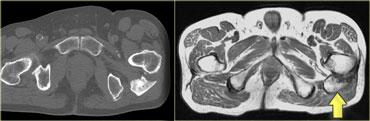

Ví dụ, ở phía bên trái là cơ thẳng đùi, có thể biểu hiện nhiều dạng phù nề khác nhau tùy thuộc vào vị trí (giải phẫu) của tổn thương.

Mũi tên màu xanh chỉ gân của đầu gián tiếp, xuất phát từ khớp háng, có hướng thẳng đứng trên hình ảnh cắt ngang này.

Dọc theo phần sau của cơ (mũi tên màu vàng), có một vùng gân dẹt xuất phát từ khớp gối.

Khi một cơ có các gân với hướng khác nhau, điều đó có nghĩa là có thể xuất hiện các dạng phù nề khác nhau tùy thuộc vào gân bị tổn thương.

Do đó, đây là dạng phù nề tương ứng với tổn thương xuất phát từ khớp gối.